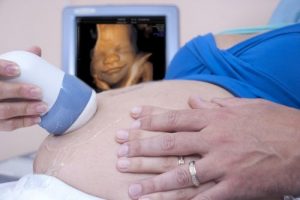

Een vrouw weet dat ze een moeder is tijdens de eerste echografie. Ze kan onmogelijk haar tranen tegenhouden bij het horen van de snelle hartslag van haar kind. Haar hart slaat al even snel, helemaal overweldigt door blijdschap door het eerste contact met haar ongeboren baby.

Instinctief zal ze haar buik beginnen te strelen. De circulaire bewegingen van haar handen zijn als een rustig en liefdevol gesprek met haar kind – een soort wiegeliedje.